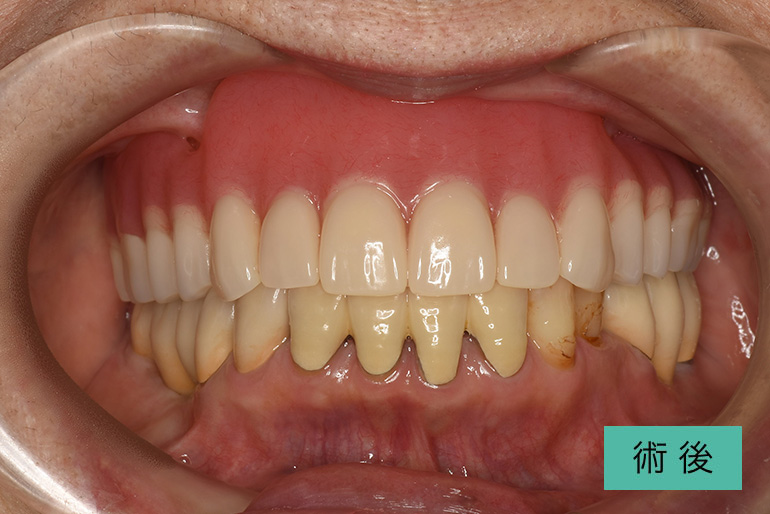

オールセラミック②

| 治療内容 | 上顎前歯右上3番から左上3番のセラミック冠 |

| 治療期間・回数 | 約1ヶ月、3回 |

| 費用(税込) | ¥990,000(165,000/1本)(補綴費用) ※自由診療 |

| リスク・副作用 | 疼痛、補綴物の脱落、咬合違和感、破折 |